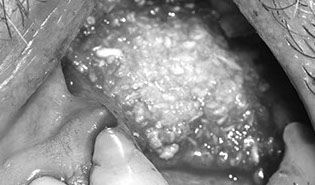

Maxillary sinus anatomy, pathology and histology

Sinus lift

Transcrestal approach

Lateral wall approach